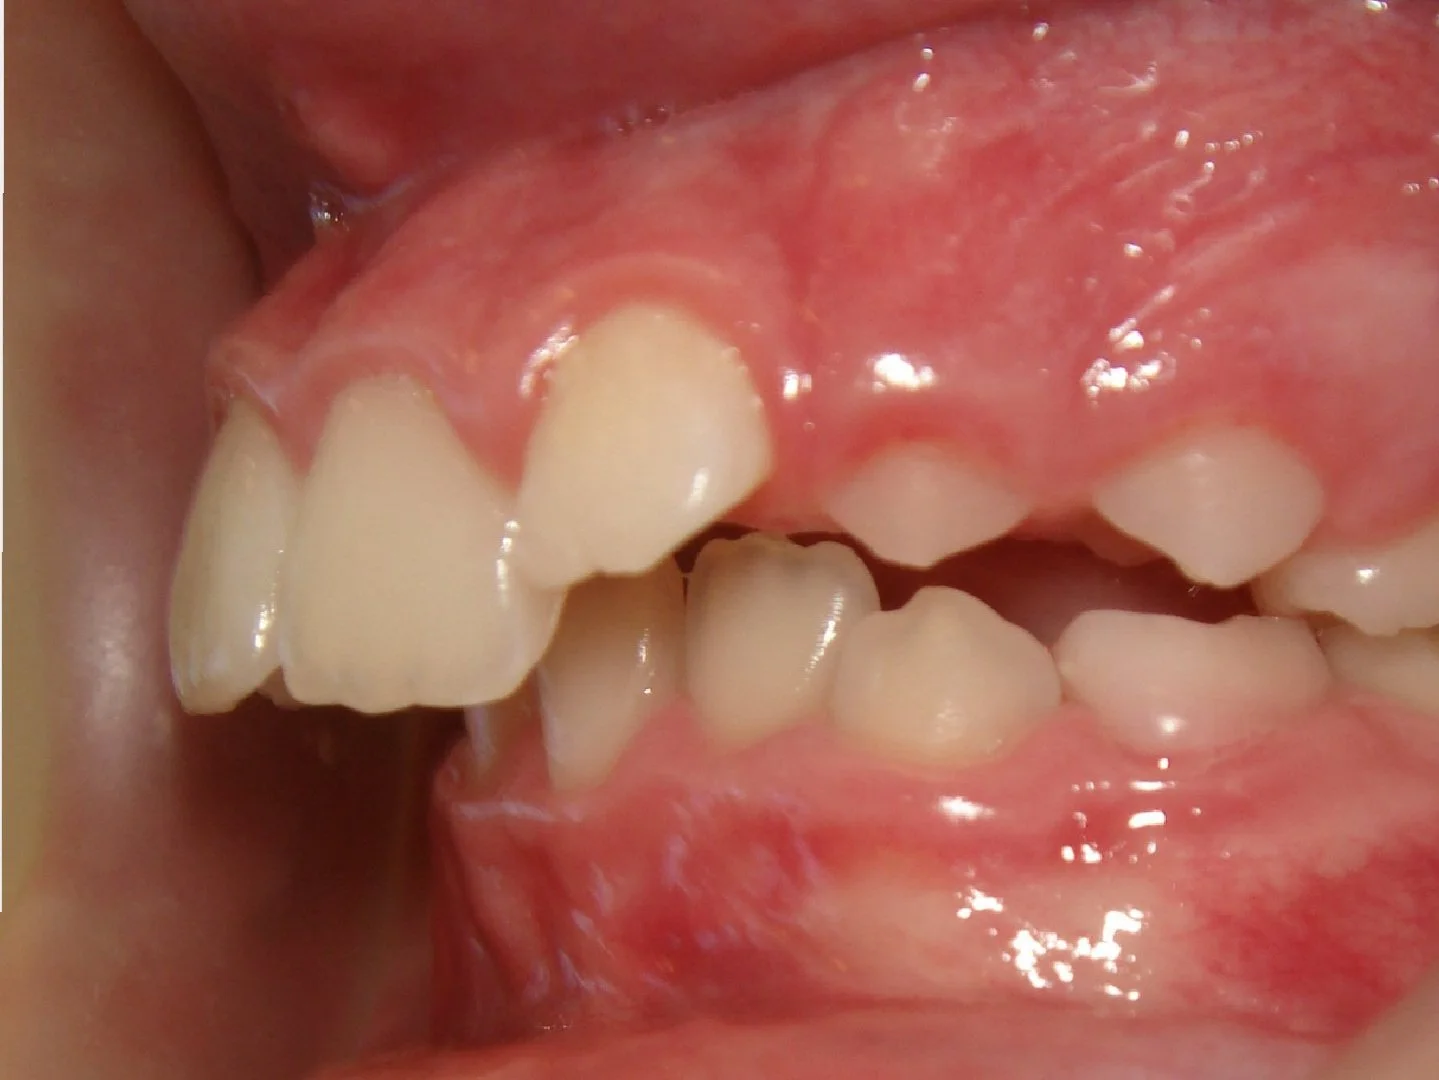

Case #1: Excess Overjet / Overbite & Crowding

Before

This 10 year old girl had crowding of her upper and lower teeth, and an extreme overjet and overbite. Her case was treated over 2 years with braces and elastics.